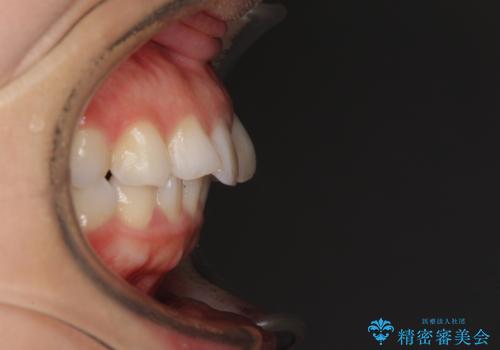

- 口元の閉じにくさと、奥歯の咬み合わせを気にして来院された患者様です。

左下の大臼歯2本が顕著に舌側に傾斜しているため、まずは奥歯の咬み合わせを改善をし、その後上下左右の第1小臼歯4本を抜歯することで口元を引っ込めながら整えることとしました。

奥歯の咬み合わせ改善には1年ほどの期間と処置中の噛みにくさを強いることとなりましたが、抜歯後はスムーズに治療を完了させることができました。

歯ぎしりの際に奥歯が干渉していた咬み合わせも理想的な状態に改善できました。